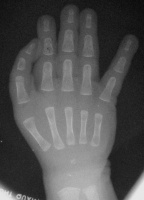

| Right hand. |

| Immediately preop. |

| The same type of procedure was performed on both hands at the same setting. This included a shortening/straightening proximal interphalangeal joint fusion and a shortening/pronating/abducting metacarpal osteotomy, along with extensor tendon shortening. Bone fixation at each site was with an intramedullary absorbable pin and intraosseous PDS sutures. Red areas are the areas of skeletal removal. |